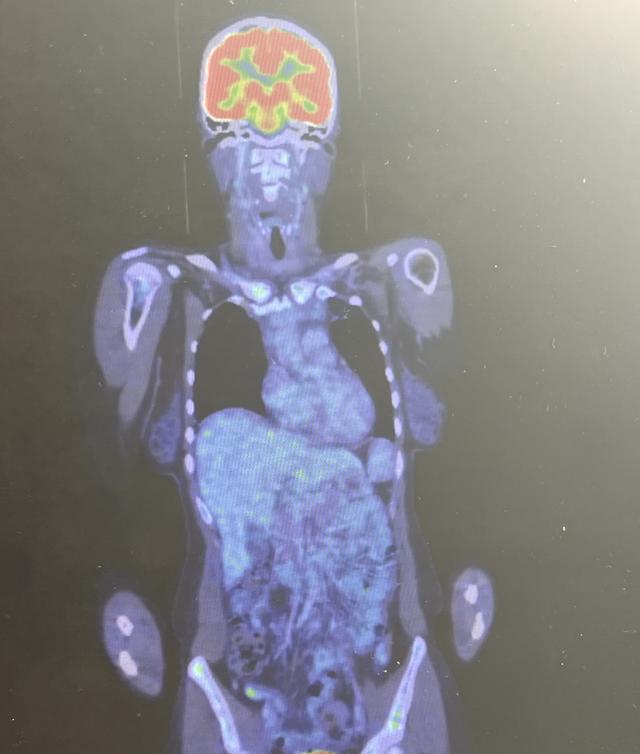

• Petscan Update 100% Complete Remission

Main image

I’m one of the living testimony that our God is Real. My faith saves me, my faith let me conquer all this trials. I didn’t give up, but indeed I have been closer to God. 💫

I have spoken to my Dr. and she said I’m in 100% Complete Remission. After 2 cycles of ABVD, I am free from Lymphoma.

From Stage 4 Hodgkin’s Lymphoma.

10cm Mediastinal Mass

3cm Lung Left Upper Lobe Mass

Hipbone Mass

To Cancer Free!!

I will continue to finish the remaining 4 cycles, they have removed the Bleomycin because it’s very toxic to the Lung, and will have AVD.